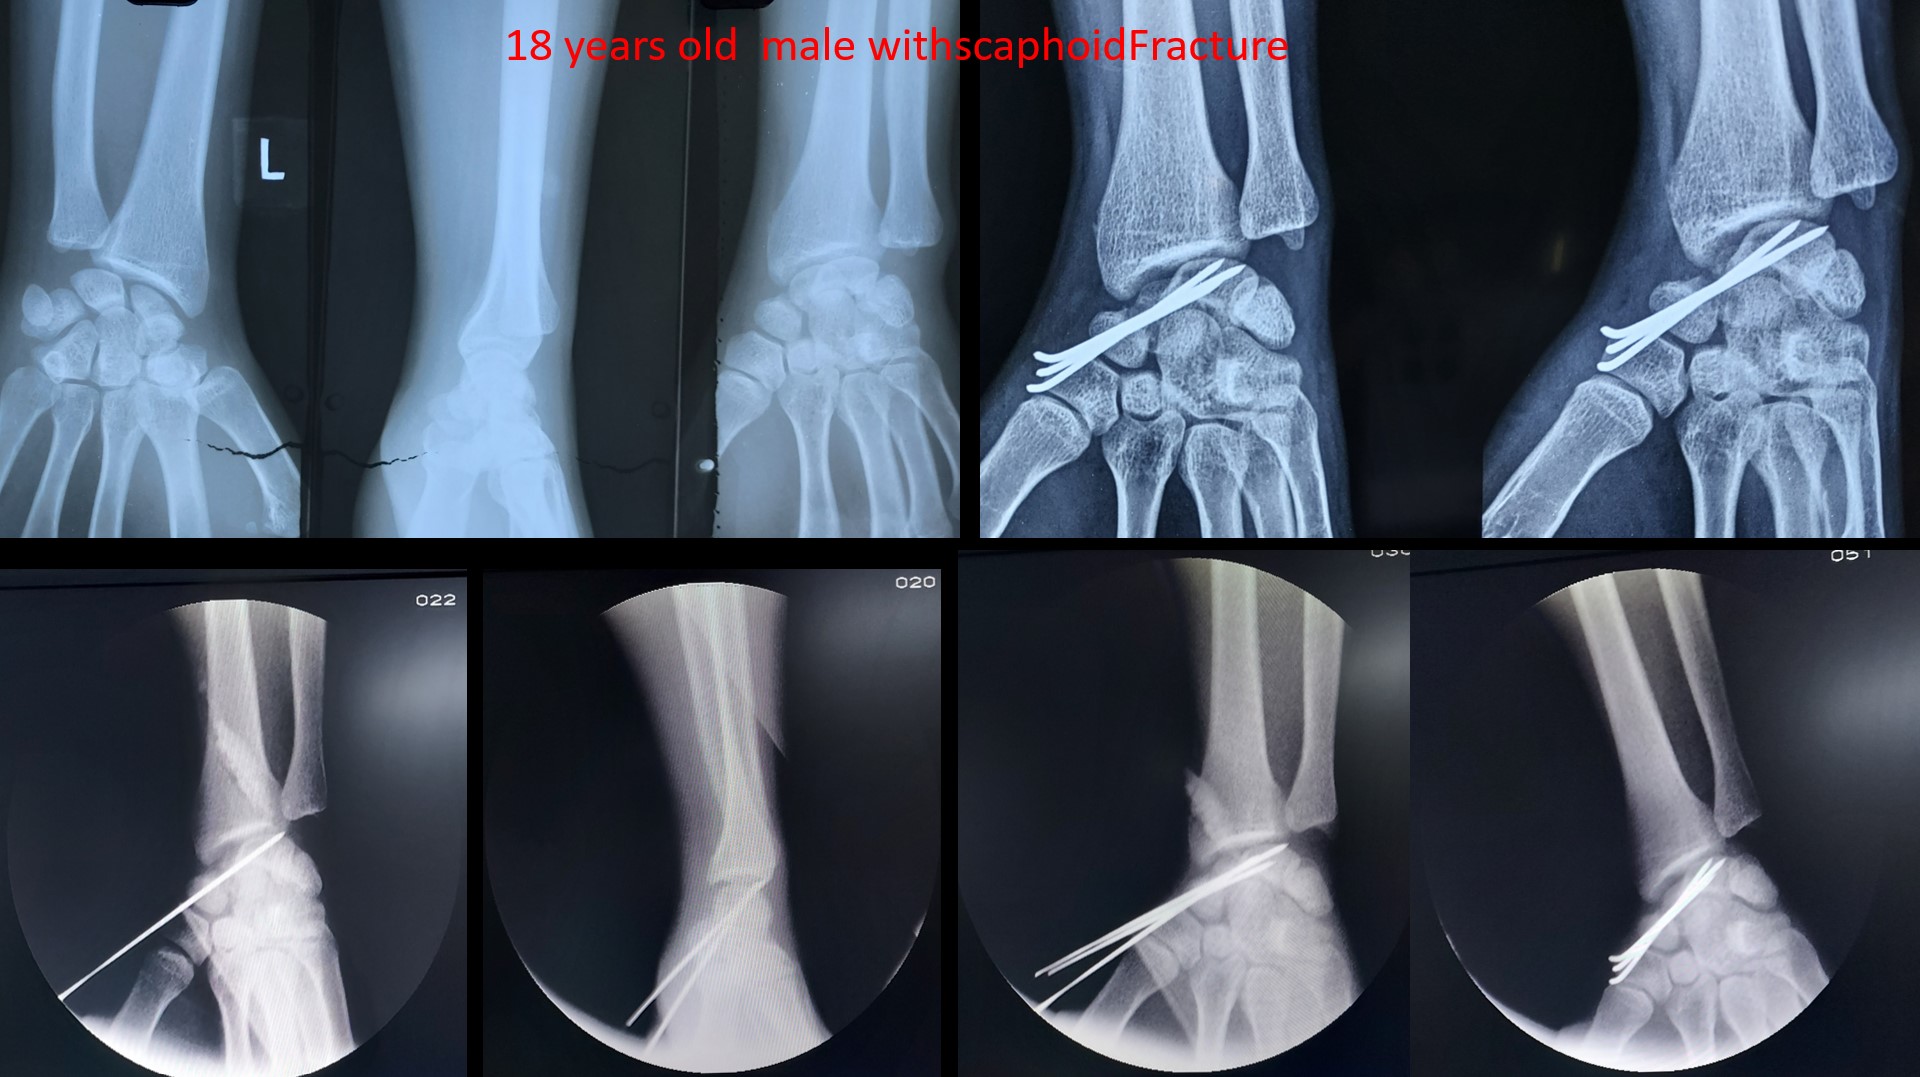

Fracture Scaphoid